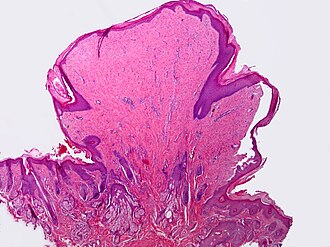

Template:Px Fibroepithelial polyp. H&E stain. | |

| LM | On a stalk / epithelium on three sides, benign epidermis, fibrous core, +/-inflammation |

Features:

- On a stalk / epithelium on three sides.

- Benign epidermis.

- Fibrous core.

- +/-Inflammation.

Micro

The sections show a fragment of skin with epithelium on three sides. The epithelium matures normally and is not hypertrophic. Orthokeratosis is present. The core of the lesion has fibrous tissue. There is no significant inflammation. No melanocytic nests are identified.